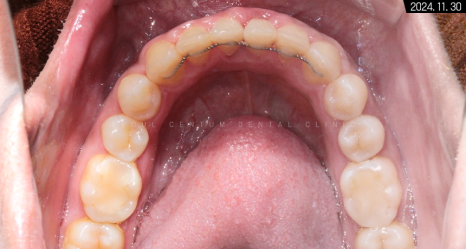

치아 교정을 바르게 마쳐서 그런지

구강을 상하측에서 봤을 때도

이전보다 가지런해진 치열이 보입니다.

중절치 중심선도 일치하고

앞니끼리 톱니바퀴처럼 견고하게 맞물려있고요.

이처럼 구치부부터 전치부까지

어느 하나 비틀어진 곳 없이

바르게 맞물리게 되었습니다.

악궁과 U자 모양도

부드러운 곡선을 갖추고 있죠.

적절히 둥근 모양이 참 보기 좋습니다.

어금니 수평 관계도 좋고 정출된 곳 없이

정상 라인 안에 치아가 모두

들어온 것을 확인할 수 있습니다.